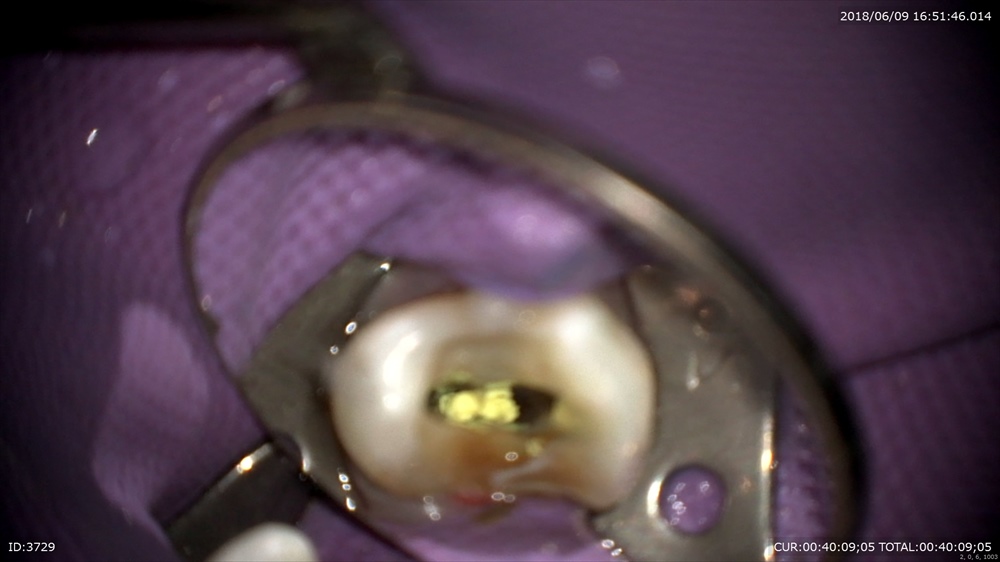

インプラントの型とり

ヒーリングから

クローズで。

次回セラミックの歯が入ります。楽しみに!!